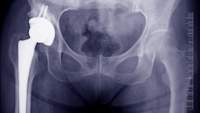

If you’ve just fractured a bone that’s vulnerable to osteoporosis (hip, spine, wrist), and have some of the risk factors (say, you’re a post-menopausal woman or have a family history of porous bones), your doctor doesn’t even have to check your bone density to know that you have the condition. The fracture alone is enough to confer the diagnosis.

不过,你的医生可能会送你一个骨密度扫描,测试测量你的骨矿物质密度(BMD)。最常见的BMD测试是一个双能X线吸收或骨密度中,被称为一个或DXA扫描DEXA。它使用的辐射水平低来衡量,即使少量的骨量丢失。它通常做了脊椎下部和臀部在放射学机构或医疗机构门诊的基础上,全程不超过30分钟。穿衣服舒适无拉链,让你的技术人员知道,如果有任何机会,你可能怀孕。您还需要避免钙补充剂在试验前24小时。